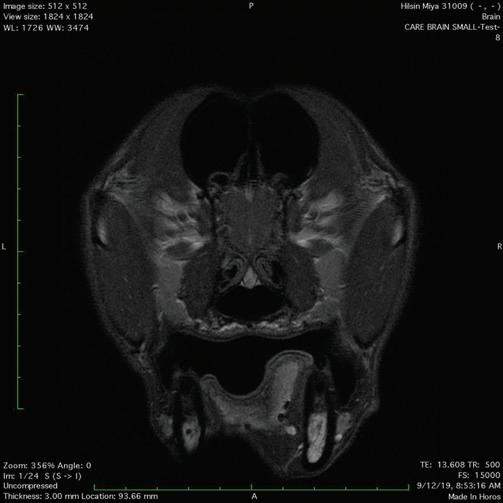

Respiratory Refresher: Diagnostics for common respiratory conditions focusing on the BAL and TTW………………………………………………………………………………………..217

The Equine Airway in an emergency setting: Focusing on tracheotomy……………………....221

Hannah R. Leventhal, DVM, MS, DACVIM

Live Equine Blind Bronchoalveolar Lavage Procedure 225